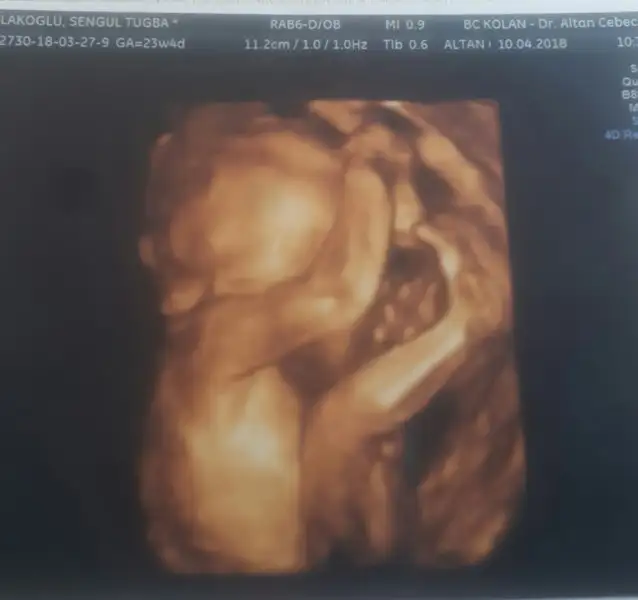

Arkadaşlar selam bugun detayli ultrasonumun kontrolü vardı 2 hafta önceki kontrolde bi değer sınıra yakın çıkmıştı suan o değerin yukselmedigini normal olduğunu ve herseyın iyi olduğunu öğrendim detaylim Allah a sükur iyi geçti çok rahatladim. Suan 23+4 uz 616 gr 29 cm olmuş resmi paylaşıyorum ama beyefendi yüzünü kapatmış ama öyle hali bile çok güzel cnm oğlum benim

Eklentiler

• 2018-04-10 13.27.20.webp

8,3 KB · Görüntüleme: 135